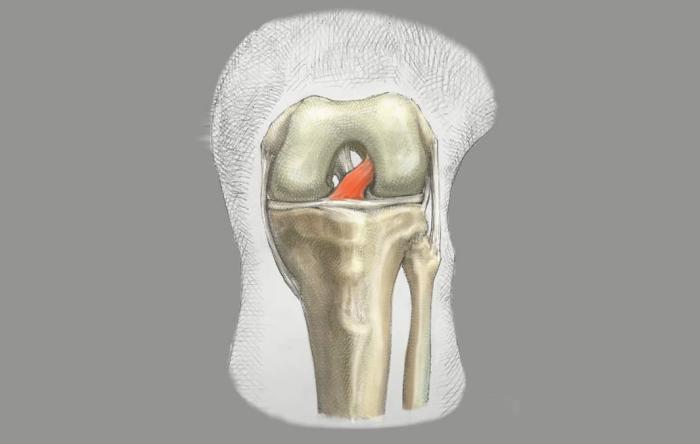

ACL Reconstruction Surgery Explained & Picking The Right ACL Graft

When it comes to selecting the best possible ACL...

ACL Repair vs. Reconstruction: Here’s the Latest

Anterior cruciate ligament (ACL) primary repairs...